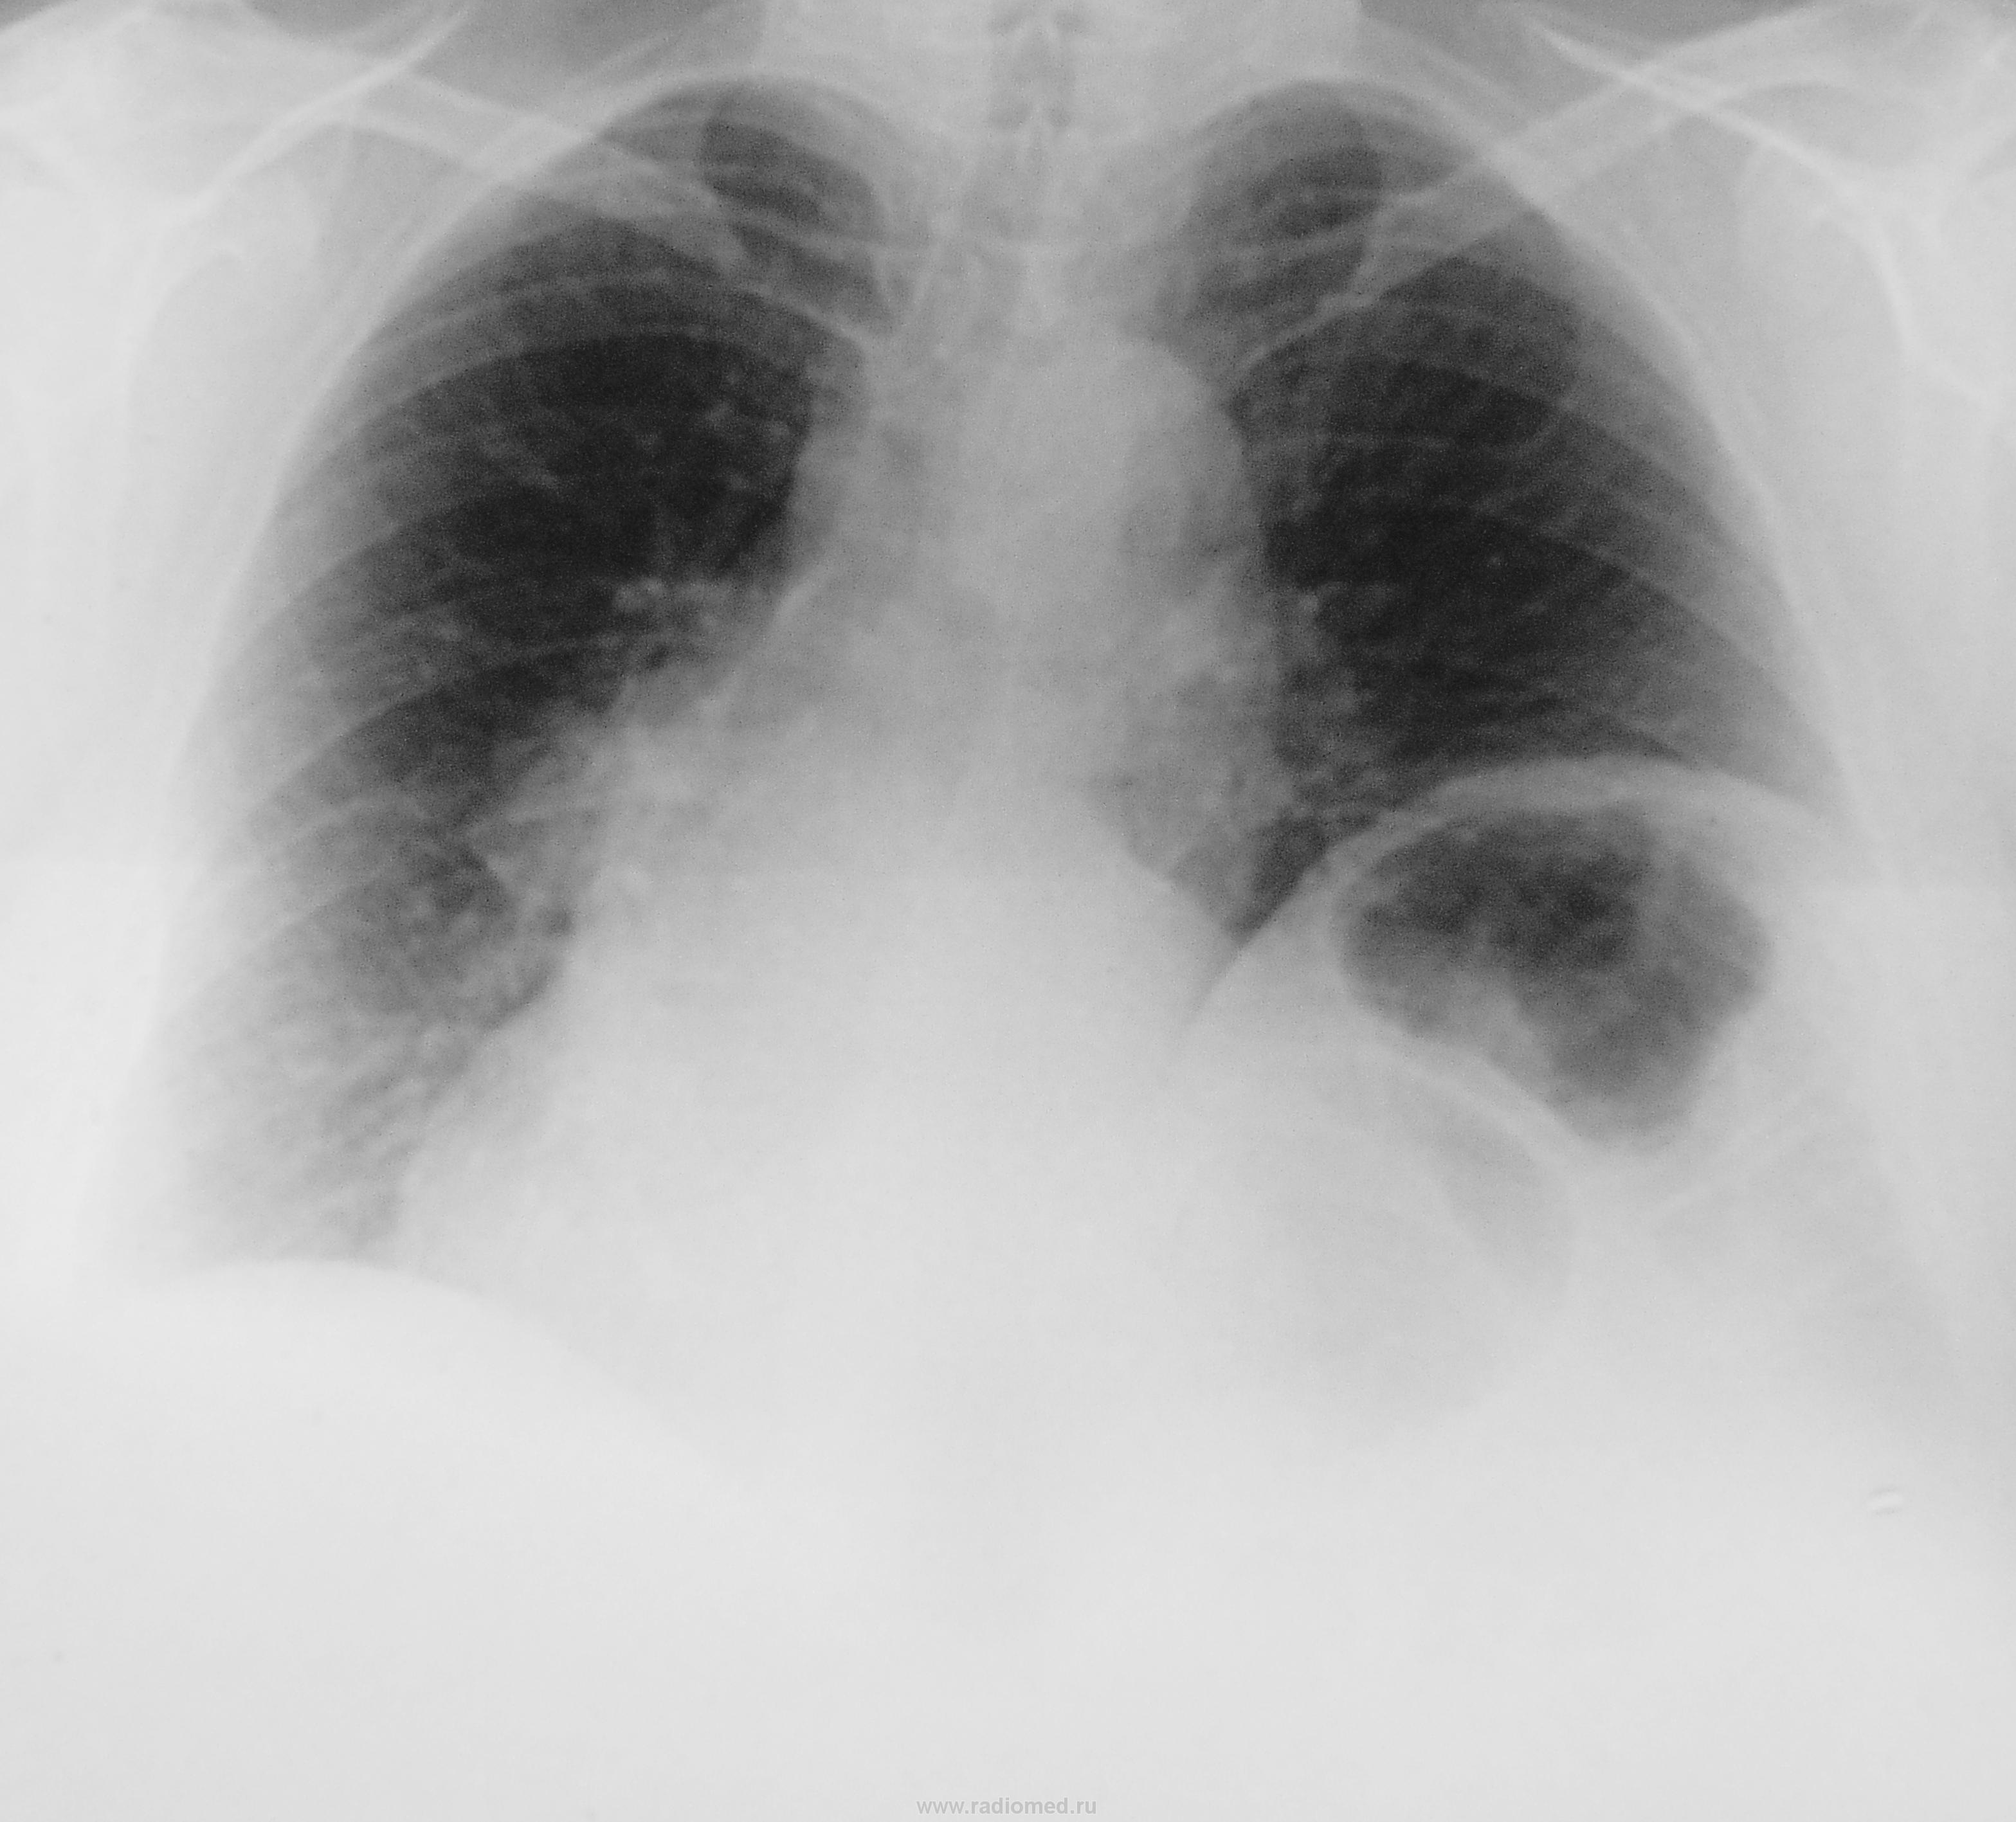

При расшифровке флюорограмм, вот такая флюорограмма. А жалобы на боли в сердце, да и у кардиолога на учёте.

Релаксация левого купола диафрагмы.

А, что понимается под "релаксацией"?

Может то, что купол диафрагмы слева выше, чем справа?

Встречается и такая релаксация. Видел несколько раз и то в пособиях и учебниках. Вначале, глядя на его сердце, подумал о ТЭЛА.

А мне что-то бронхиальное дерево слева не понравилось. Уже томограммы хочется).

Релаксация.. Элевация.. Не исключается грыжа левой половины купола (был у меня один паренек - выглядело, как релаксация, поступил с заворотом желудка, контраст лишь до кардии дошел, на операции была грыжа купола, ворота рассекли, желудок выправили). А газ в кишке и давит. Симптоматика будет кардио-симулирующей. Сердце увеличено и смещено. Стенки бронхов обызвествлены и грубо деформированы.